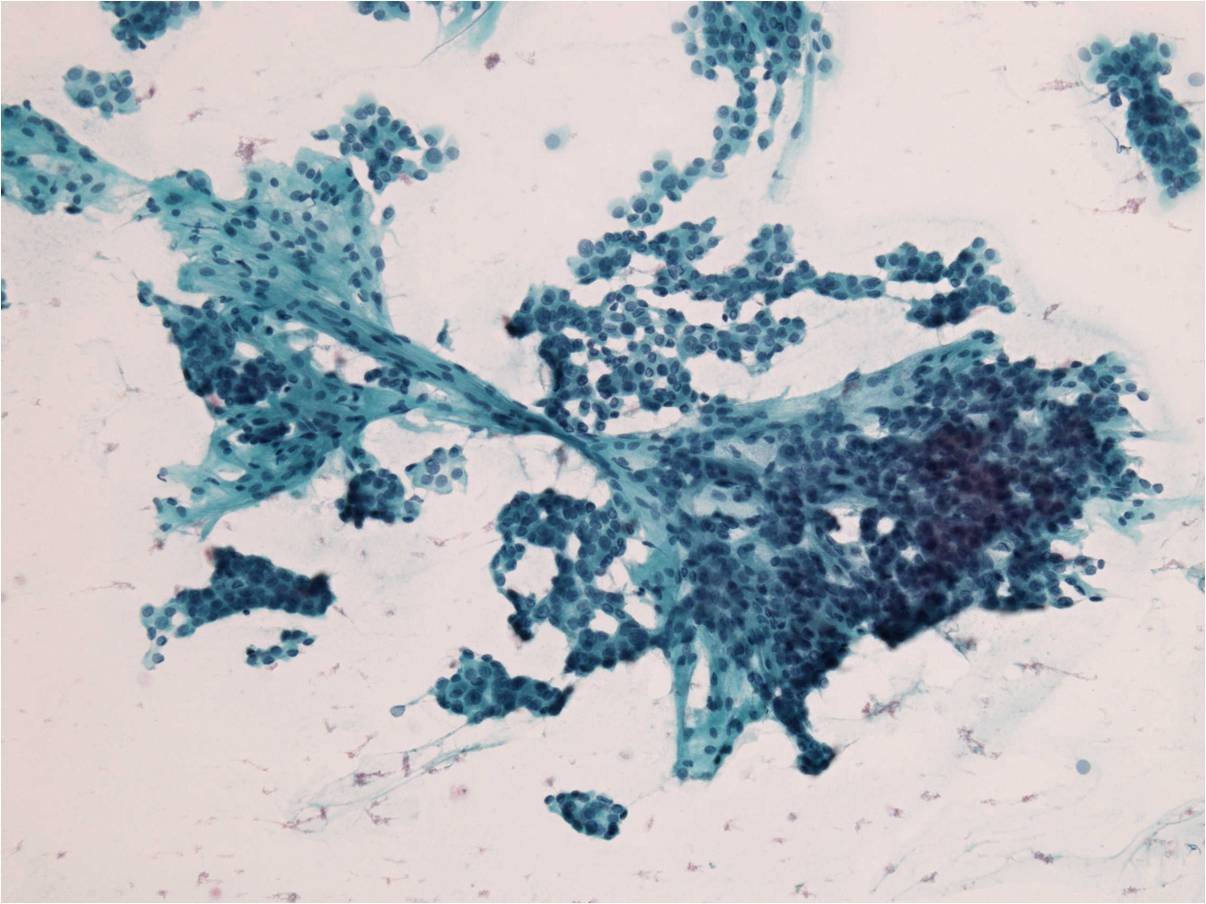

細胞診所見

血性背景、コロイドはほとんどなし。

核溝および核内封入体を散見する血管結合織を伴った乳頭状の異型細胞集塊、ならびに濾胞状構造を示す異型細胞集塊が認められた。